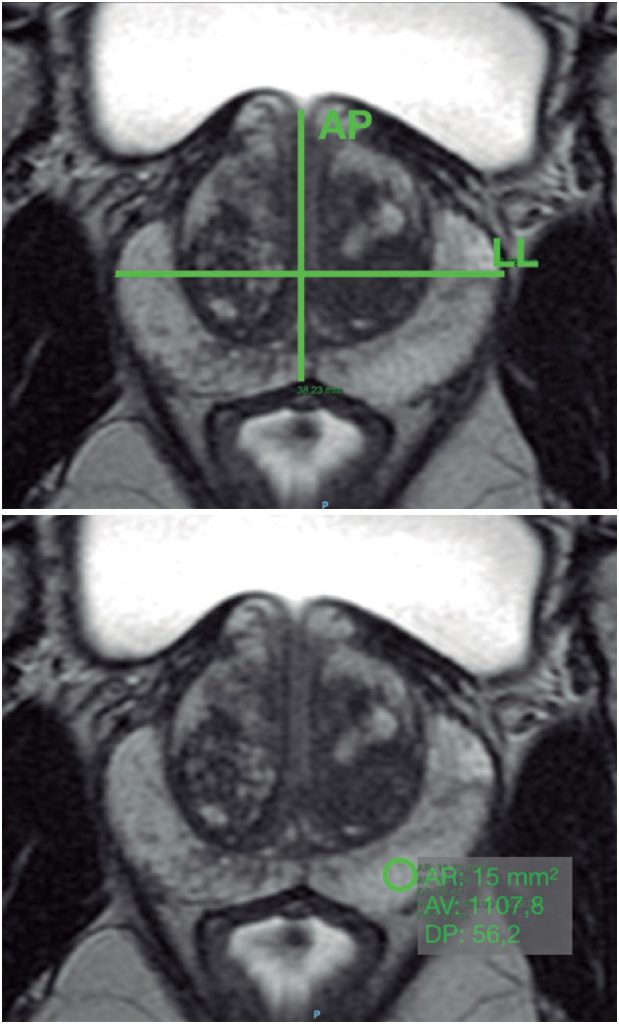

Comparar qualitativa e quantitativamente, em termos de qualidade de imagem, um novo protocolo de sequência de difusão biexponencial com o protocolo de difusão monoexponencial padrão, em ressonância magnética multiparamétrica da próstata.

Estudo com coleta prospectiva e análise transversal. Entre agosto e novembro de 2017, foram recrutados 70 pacientes que realizaram ressonância magnética multiparamétrica da próstata, por suspeita de neoplasia prostática. As imagens obtidas por ambas as sequências foram avaliadas por dois leitores independentes, quanto a critérios de avaliação subjetiva/qualitativa (seis critérios) e objetiva/quantitativa (três critérios), sempre comparando os protocolos de aquisição monoexponencial e biexponencial. Os resultados foram comparados por análise estatística (concordância interobservador − coeficiente de Gwet; análise das variáveis qualitativas − teste de Stuart-Maxwell; e análise das variáveis quantitativas − testes de Wilcoxon).

Após exclusão de quatro pacientes, a amostra final foi composta por 66 pacientes. Uma boa/excelente concordância interobservador foi estabelecida para critérios subjetivos (exceto em um critério). Para a análise qualitativa, a quantidade de avaliações boas ou excelentes foi maior para o protocolo monoexponencial (exceto em uma categoria), com evidências de diferenças significativas para três critérios (qualidade global da imagem ponderada em difusão, relação sinal-ruído na imagem ponderada em difusão e relação sinal-ruído ADC). Para a análise quantitativa dos dados, o protocolo monoexponencial apresentou menor variabilidade dos diâmetros anteroposteriores, o que significou menos distorção das imagens, e melhor relação sinal-ruído estimada.

Em nossos dados, a qualidade das imagens da sequência de difusão padrão monoexponencial foi qualitativa e quantitativamente superior àquelas da sequência teste biexponencial.